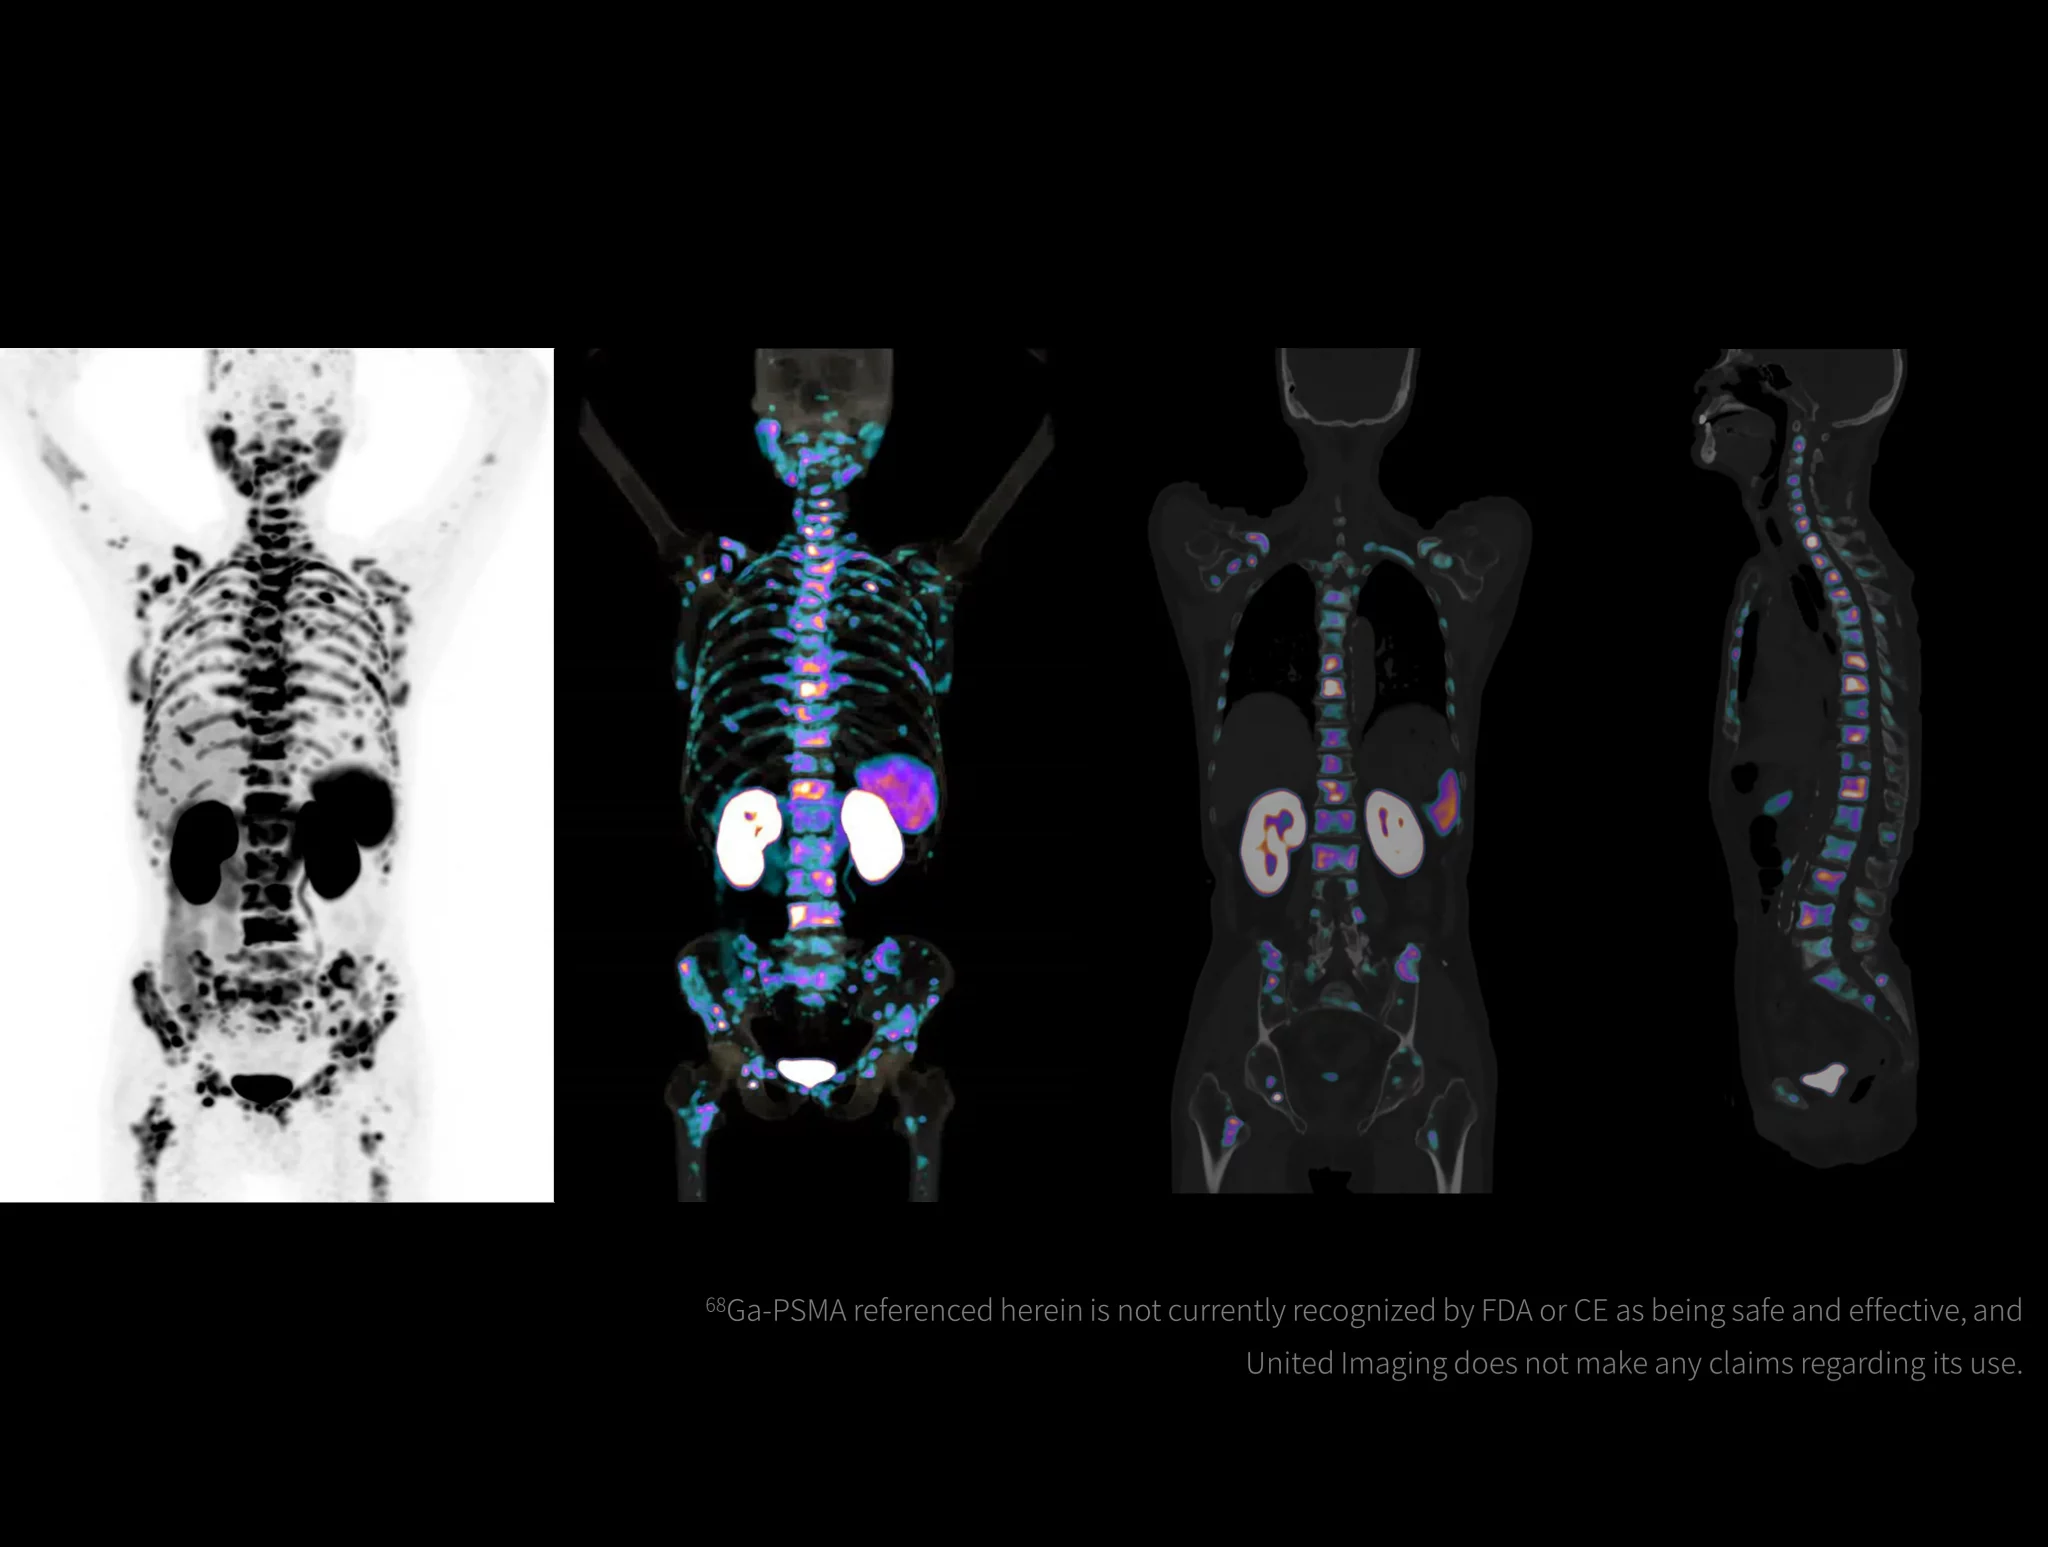

With the ultra-high system performance, uMI Panorama faces up to the challenges of tracers with different half lives and the complex scanning conditions, without compromise for image quality.

Click on different tracers to see the images.

Case Gallery

4 Measured on uMI Panorama 28 and uMI Panorama 35 with TOF gain calculated with a 35-cm cylindrical phantom.United Imaging does not make any claims regarding the safety and effectiveness of tracers that have not been approved by the FDA or CE.